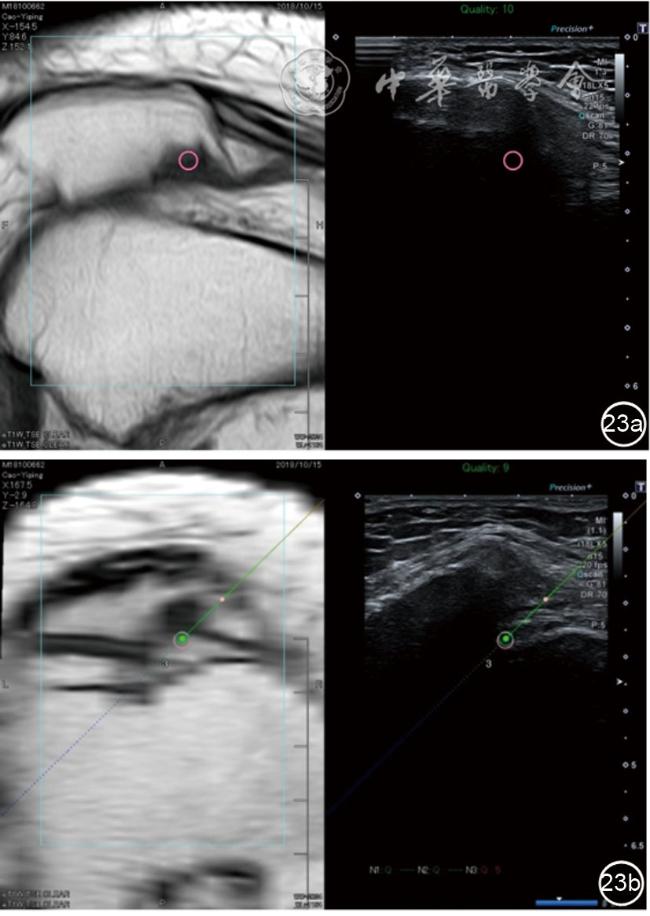

3.膝关节内局部治疗。随着病情发展,静态结构失衡,膝关节内部结构发生变化,会出现软骨损伤、脱落,关节间隙变窄,内外间隙不等,骨赘形成等。膝关节内局部治疗包括关节内症状性骨赘剥离、玻璃酸钠及PRP注射等。(1)膝关节内症状性骨赘针刀剥离松解治疗。由于软骨缺损或者力平衡失调,在关节内脱落软骨区会出现骨赘。部分骨赘引起疼痛,或者与髌骨撞击出现临床症状需要治疗。针刀剥离目的不是去除骨赘,而是剥离松解,缓解或者消除疼痛。以股骨外髁骨赘为例。患者平卧位,膝关节屈曲100°~120°。一般选用10 MHz超声探头,穿刺区域常规消毒,探头涂抹耦合剂后套入无菌手套碘伏消毒或使用无菌耦合剂。将探头置于患者皮肤表面,短轴扫查,显示关节面与骨赘,选用25G注射针,抽吸1%利多卡因3 ml于骨赘周围进行分层麻醉。选用直径1 mm的Ⅰ型2号针刀,在超声引导下从外侧向内侧到达骨赘,反复剥离,一般5~8刀后拔出针刀结束治疗(图18),局部压迫5分钟,无菌敷料覆盖。(2)膝关节髌上囊积液治疗。髌上囊积液在膝关节骨关节炎比较常见,尽管积液量可能很大,但通过软组织松解治疗后,大部分患者积液会减少或者消失。所以积液的治疗可以放在后面处理。超声引导下抽出积液,药物注射是常用的治疗方法。膝关节炎积液的治疗通常包括关节内皮质类固醇激素或者臭氧注射。如果慢性以滑膜丛型增生为主,针刀有限切割增生滑膜加药物注射可提高疗效。①髌上囊积液抽吸加臭氧注射治疗。患者平卧位,膝关节屈曲30°~60°,膝下垫一软枕。选用10 MHz超声探头,治疗前消毒准备同骨赘针刀剥离松解治疗。将探头置于患者皮肤表面,短轴扫查,找到积液最多处,应用22G针头,直接穿刺进入髌上囊抽出液体,然后根据髌上囊大小制备35 μg/L的15~20 ml臭氧注入髌上囊内拔出针头(图19),局部压迫2分钟,无菌敷料覆盖。②髌上囊慢性滑膜炎针刀切割松解治疗。患者平卧位,膝关节屈曲30°~60°,膝下垫一软枕。选用10 MHz超声探头,治疗前消毒准备同骨赘针刀剥离松解治疗。将探头置于患者皮肤表面,长轴或短轴扫查,找到积液最多处,用一次性5 ml注射器抽吸1%利多卡因3 ml于髌上囊进行分层注射麻醉,囊内也要注射适量麻药,尽量抽出积液。选用直径1 mm的Ⅰ型2号针刀,长轴扫查从近端向远端,短轴扫查从外侧向内侧,在超声引导下进入囊肿内对内壁及增生滑膜的不同方向、角度进行反复切割(图20),一般2~3分钟拔出针刀,然后囊内注射1%利多卡因3 ml+曲安奈德15 mg,结束治疗,局部压迫5分钟,无菌敷料覆盖。(3)膝关节腔PRP注射治疗。关节腔注射主要是为了修复软骨,如果不是为了治疗积液,不主张应用激素类药物。目前主要的注射药物为玻璃酸钠、PRP。按照传统的注射部位,多为髌上内、外或者髌下内、外注射点,但是超声不能观察到注射针的位置,药物也不能很好到达软骨损伤的部位,效果受到影响(图21)。膝关节软骨损伤的主要部位在髌股关节的股骨髁,超声可以很好地显示这一部位,并能显示软骨变薄。因此,由这个路径平面内进针注射,可以很好显示穿刺针的路径与位置。以注射PRP为例。患者平卧位,膝关节屈曲100°~120°,选用10 MHz超声探头,治疗前消毒准备同骨赘针刀剥离松解治疗。将探头置于患者皮肤表面,短轴扫查显示关节面,应用25G注射针头,抽吸1%利多卡因2 ml由内侧进针进行分层麻醉直达关节软骨面。制备4.5 ml PRP,直接注射到关节面,液体顺关节面分布,注射完毕拔出针头(图22)。局部压迫2分钟,无菌敷料覆盖。(4)髌骨软化超声影像融合技术下PRP注射治疗。髌骨软化是指髌骨关节面的软骨损伤,软骨下骨囊变,MRI能够明确诊断,但是超声不能显示。应用超声与MRI的影像融合技术,依据MRI明确注射部位,在超声引导下可将药物精准注射到软骨损伤的部位。患者平卧位,膝关节屈曲30°,下面垫一软枕。一般选用10 MHz超声探头,治疗前消毒准备同骨赘针刀剥离松解治疗。将MRI的原始图像数据导入超声设备中,进行手动影像融合,完全融合后,确定穿刺靶点,以MRI图像为目标,以超声图像为实时引导进行穿刺,到达目标后,注射提前制取的PRP 3 ml(图23),注射完毕拔出针头,局部压迫3分钟,创可贴覆盖。

图23 髌骨软化MRI与超声影像融合技术下富血小板血浆注射治疗图像